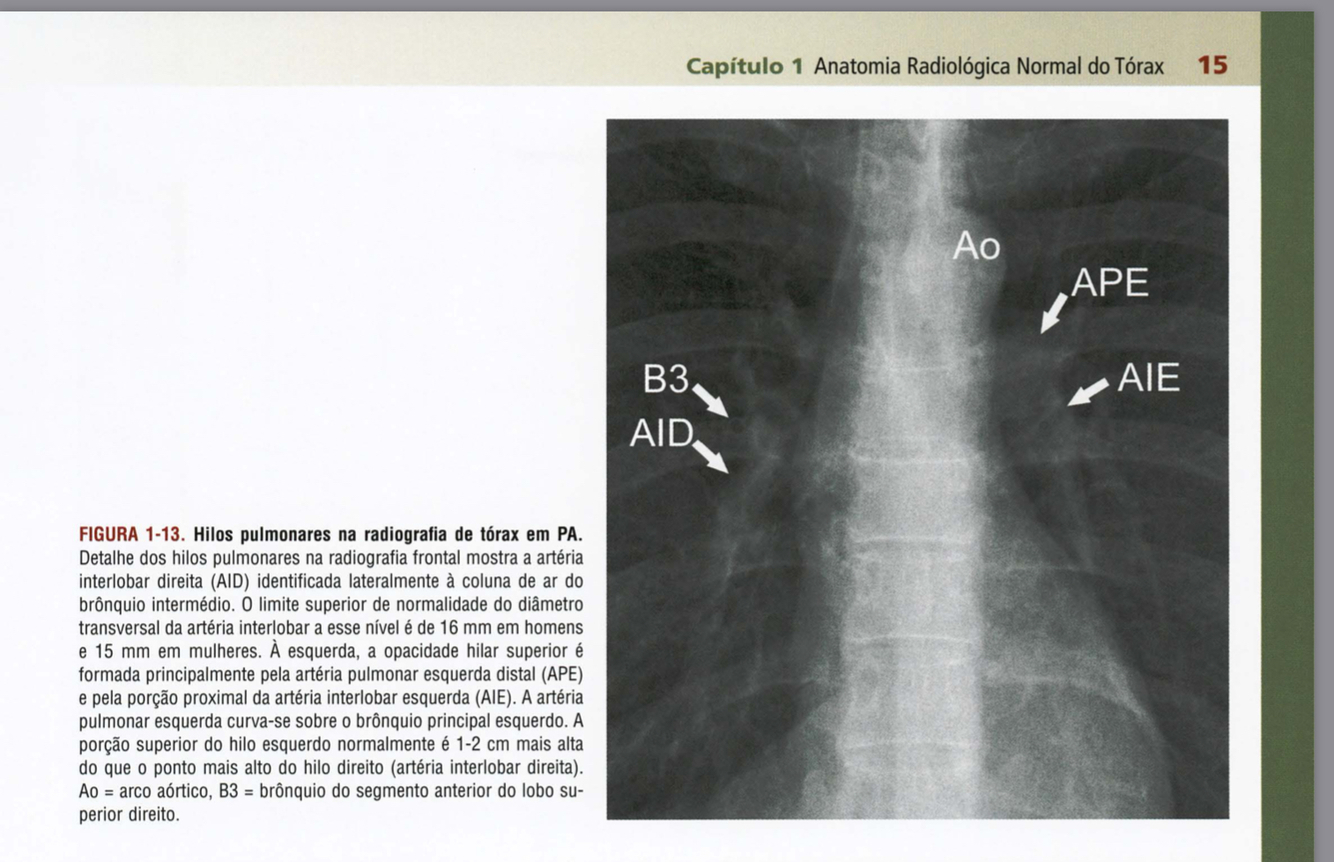

Qual estrutura apontada?

Qual a estrutura apontada?

Quais são as estruturas apontadas?